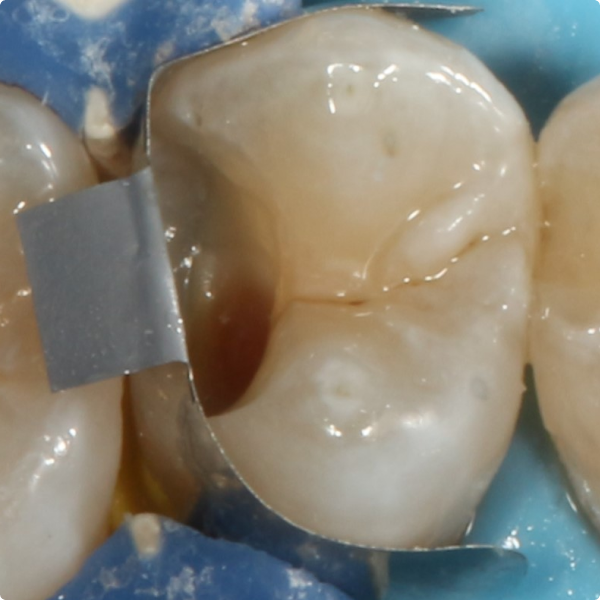

When a 17-year-old patient arrived for a routine six-month check at Dr Kiran Shankla’s practice, there were no complaints or concerns raised by the patient. During the examination a subtle colour change was observed on the upper left premolar. A bite-wing X-ray revealed a cavity, further confirmed with the aid of software.

Although Stela can be used without a rubber-dam, Dr Shankla opted for one to maintain optimal isolation and control. After removing the decayed tissue, photographs were taken to document the cavity’s extent. A sectional matrix was placed to ensure proper contact, given the size of the lesion, then the Stela system was applied.